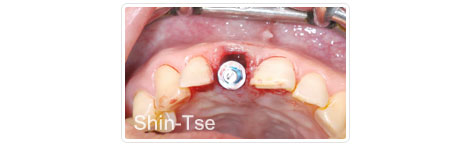

前牙單根即拔即種

病患左上大門牙舊假牙脫落。經X-光診斷有根尖囊腫且牙根已斷裂!!

將病灶囊腫徹底清創後立即植入,沒有放骨粉,也沒有翻瓣開刀。

植牙後

四個半月後完成贋復牙冠。